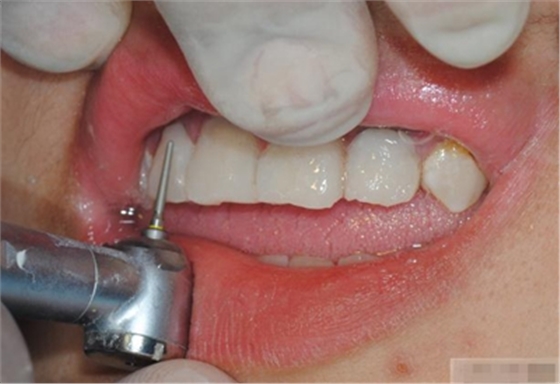

【初步修整】

對(duì)于唇面,首先使用火焰狀車針進(jìn)行修整,一般不使用輪狀車針修整線角

微細(xì)的表面結(jié)構(gòu)最后使用鎢鋼拋光車針成形的。

修整完成

拋光目的:表面光滑 咬合關(guān)系 邊緣適應(yīng) 最少的菌斑附著 易于菌斑去除 美觀性

【纖維刷拋光】

脂拋光中應(yīng)注意:樹脂拋光放到24H后為最佳,因?yàn)榇藭r(shí)收縮應(yīng)力最為平衡,特別是在固化后10min內(nèi)應(yīng)避免對(duì)樹脂修復(fù)體進(jìn)行外力加載,包括打磨拋光及冷熱張力等,因?yàn)榇似陂g收縮應(yīng)力變化明顯,拋光時(shí)的機(jī)械應(yīng)力會(huì)使釉質(zhì)層形成裂隙。